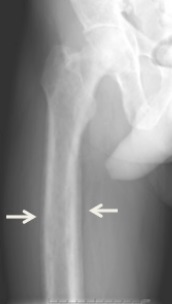

Conditions due to bone loss such as osteopenia and osteoporosis are common in tertiary hyperparathyroidism along with pathologic fractures. Pseudoclubbing of the digits can also be indicative of a severe tertiary hyperparathyroidism due to excess resorption at the distal phalanges.[8][1]

Diagnosis includes both clinical and laboratory investigations. Radiological investigations include looking for signs of bone loss in both the hands and pelvis which is characteristic of tertiary hyperparathyroidism.[8] Other clinical examination can include grading of muscle weakness, which is done by asking the patient to stand from a seated position with their hands folded across their chest.[4][8] Laboratory investigations include evaluating blood calcium and alkaline phosphatase, which are always increased in tertiary hyperparathyroidism. Other common results from laboratory investigations would include decreased vitamin D levels, elevated blood parathyroid hormone and hyperphosphatemia.[9][8][1][4]